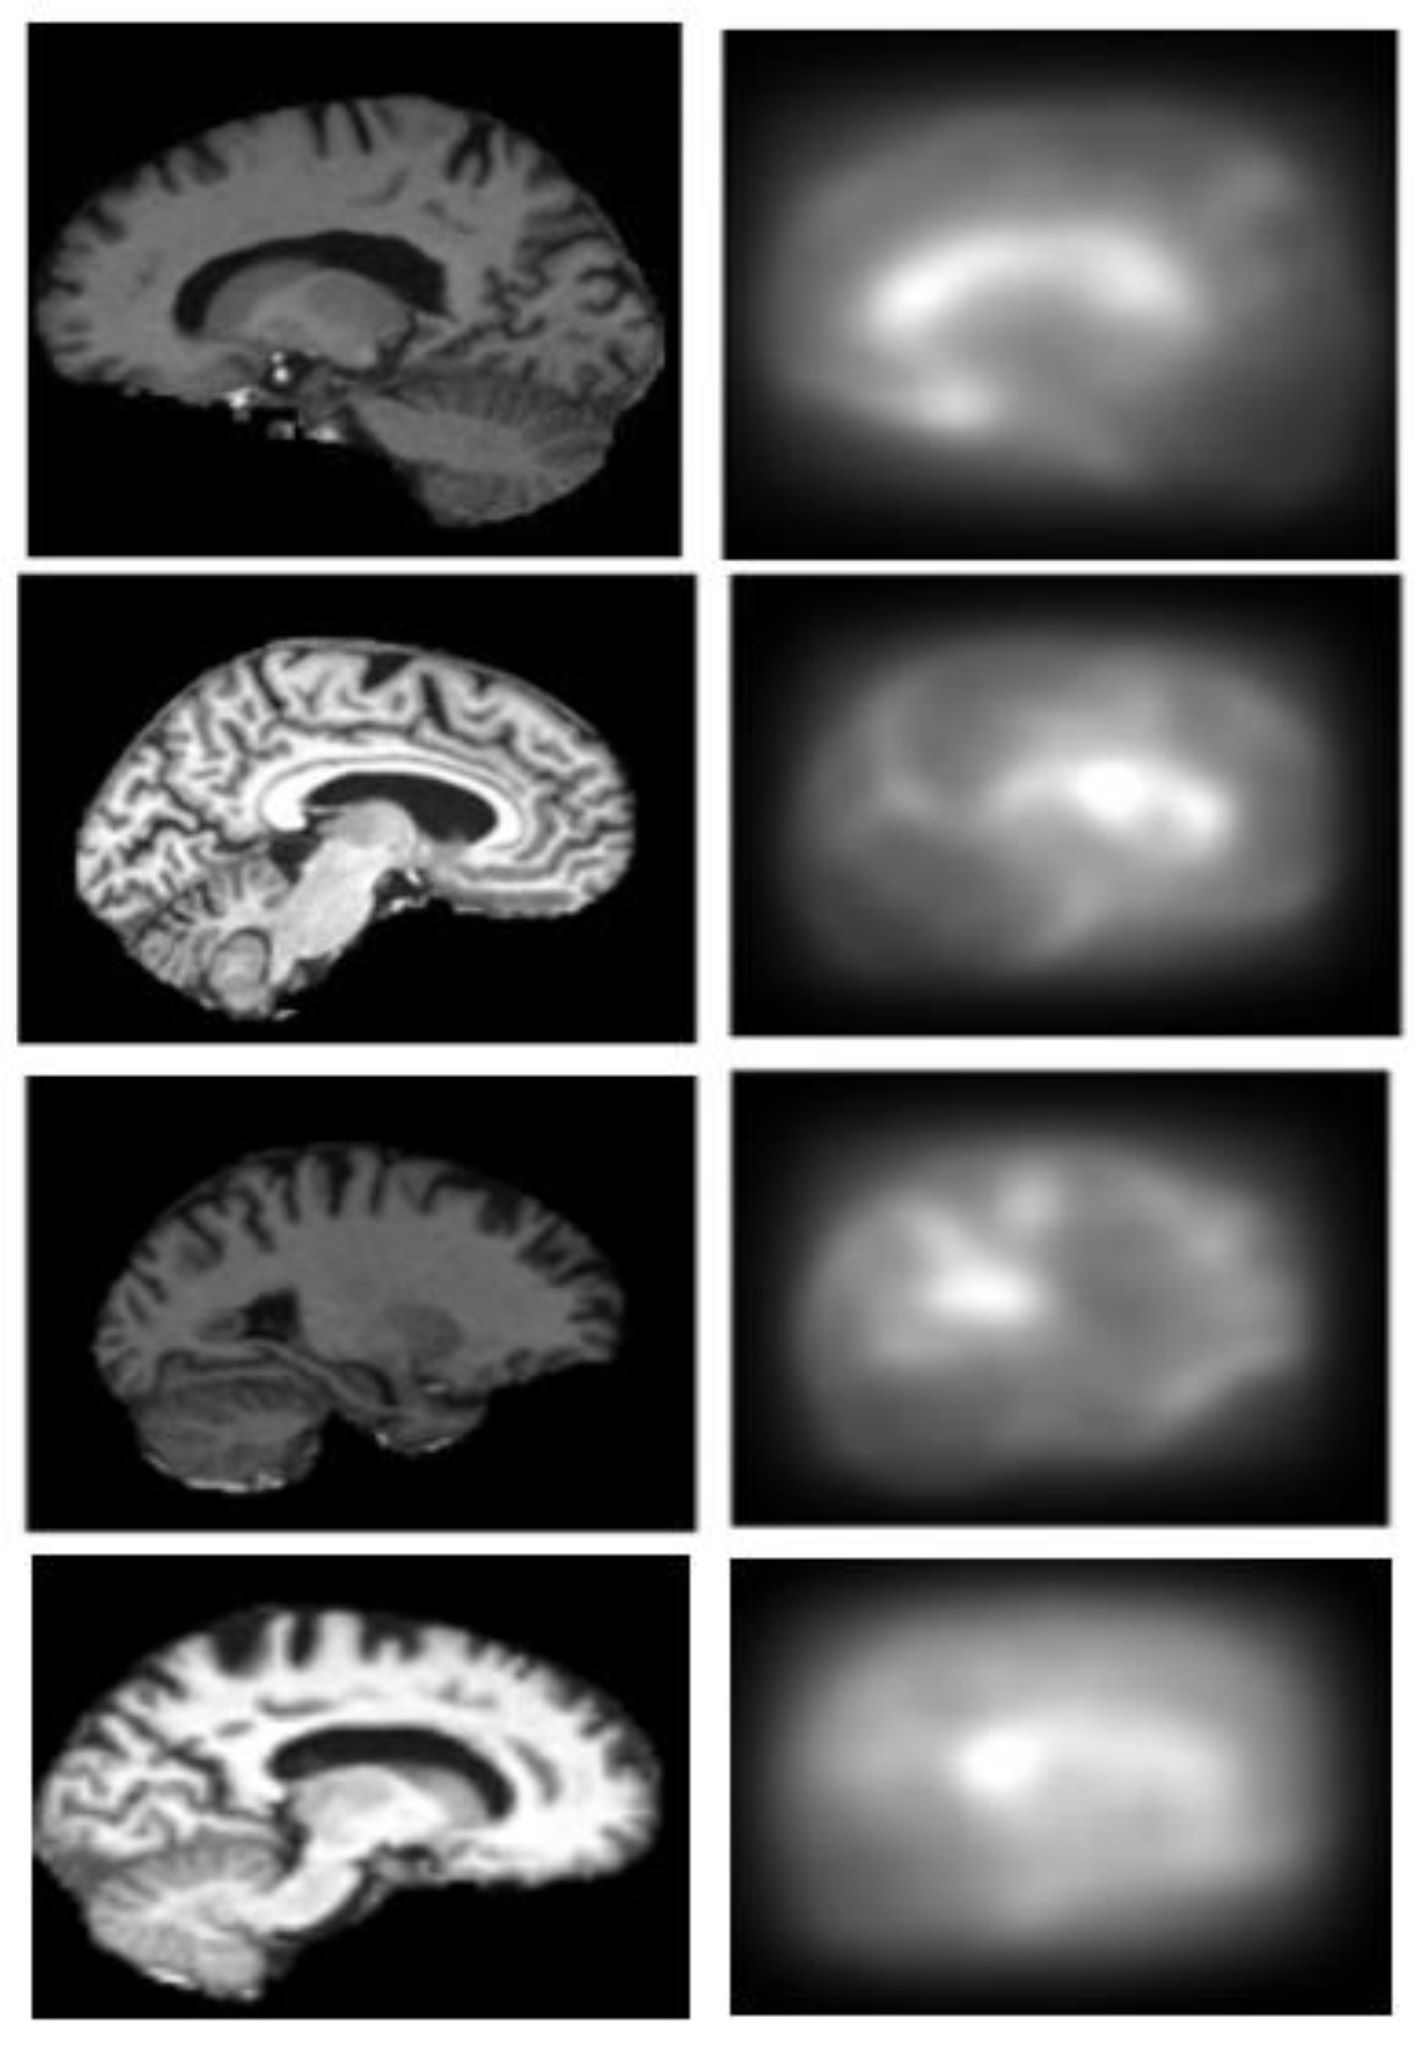

2.3. Generation of Saliency Maps

2.3.1. Top-Down Saliency Maps (

2.3.2. Bottom-Up Saliency Maps (

2.3.3. Final Saliency Map